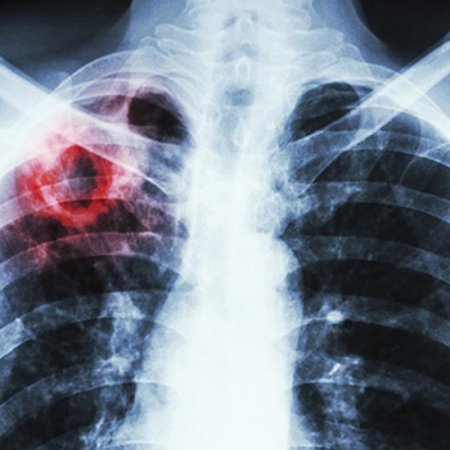

Хвороба шириться шаленим темпом: На Закарпатті прискорюють завершення будівництва туберкульозної лікарні

Якщо наприкінці 2021 року Закарпаття було у трійці регіонів за кількістю виявлених випадків захворюваності на туберкульоз, то за перші місяці 2022 року опинилося на другому місці. Зважаючи на всі фактори і ризики, на жаль, мусимо констатувати, що недуга буде і надалі поширюватися. І то стрімкими темпами – пише на своїй сторінці у фейсбуці перший заступник голови Закарпатської ОВА Мирослав Білецький. Саме тому завершення будівництва туберкульозної лікарні у Нижній Апші на Тячівщині особливо актуальне. У перші тижні і місяці війни всі рахунки були заблоковані, тож провести оплату за виконані роботи, закупити необхідні будматеріали було неможливо. Тому роботи на об’єкті зупинилися. Зараз відповідно до внесених змін Мінфін послабив обмеження щодо здійснення платежів і закупівель, які здійснюються у межах реалізації міжнародних грантових проєктів. Хочемо використати цей час та сприятливі для будівельних робіт погодні умови, аби завершити проєкт. Так, суттєво зросли ціни на паливо, матеріали, однак ми сподіваємося на підтримку іноземних партнерів, які можуть допомогти нам втілити проєкт у життя. Для Закарпаття та всього Західного регіону України важко переоцінити значення та важливість відкриття цього закладу в умовах війни, міграції, стрімкого поширення різних недуг.